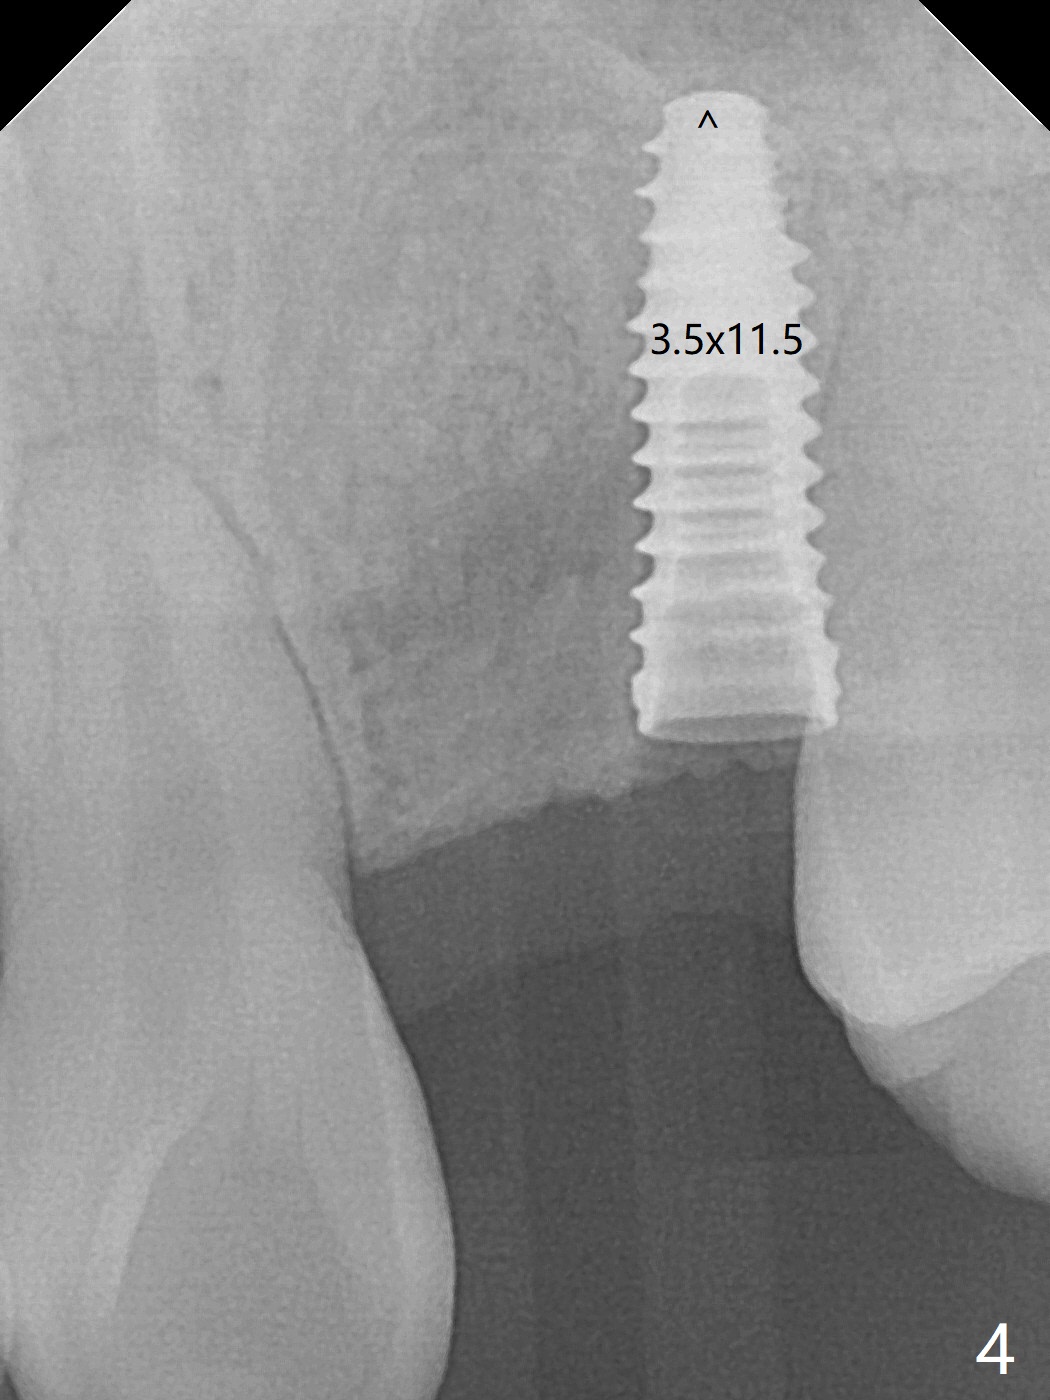

18岁男,本月底到外州上大学,急于十九岁前完成治疗,保险可以多付些。术前检查显示双侧尖牙(图一,二 6,11)根尖,侧切牙牙槽嵴萎缩(*),尖牙、侧切牙之间颊侧做垂直切口,骨膜下潜行分离,在尖牙根尖隧道植骨,然后使用导板,植入窄植体(图四至六),接近或者穿过上颌窦底板(图三,四箭头),骨粉(粘性骨块做的不成功,图五,六 *)好像覆盖暴露的螺纹。再次补充隧道骨粉后,放置修复基台(图七,八),调整后(图九),取模做临时悬臂桥,临床上有些困难分配尖牙,侧切牙比例。术后4个月左侧植体愈合正常(图十,十一),而右侧感染。